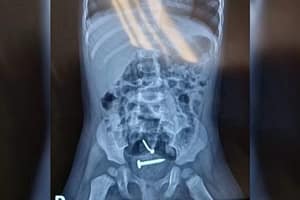

Parafusos no corpo da menina

Elas foram encaminhadas para o hospital e, após a realização dos exames, um raio-X apontou a presença de objetos estranhos dentro do corpo da menina. Ela também tinha lesões nas partes íntimas.